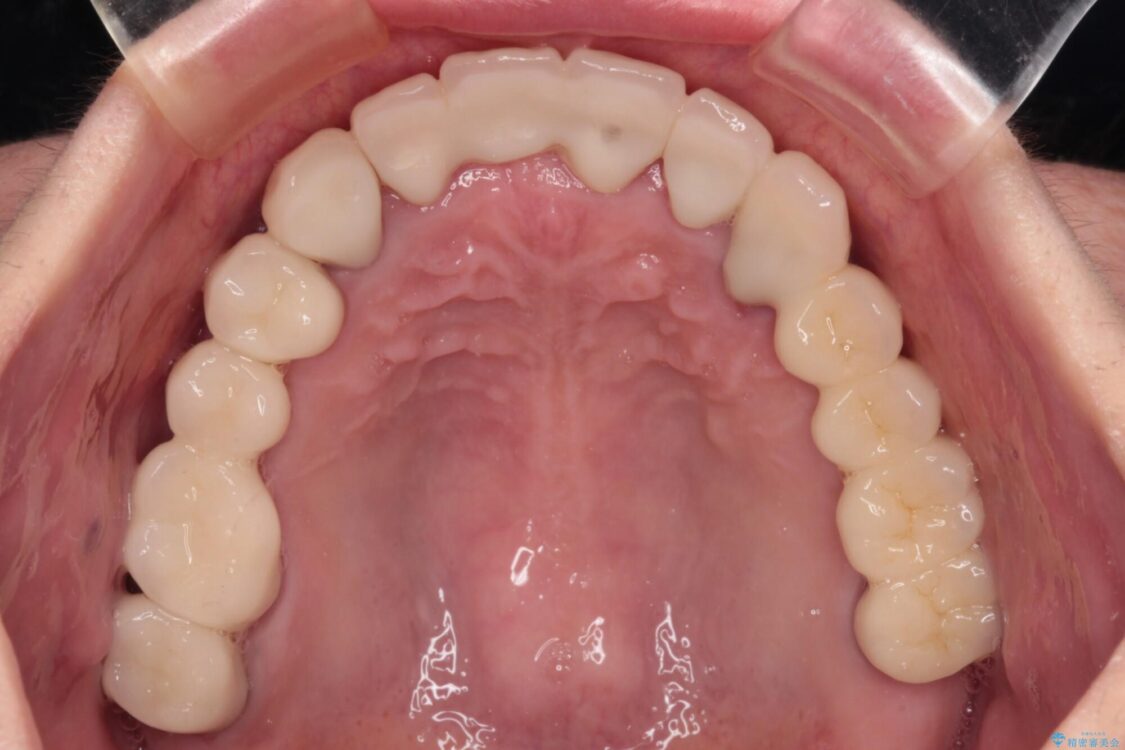

治療後

• 放置したインプラントとインビザライン 全顎リカバリー治療 治療後画像